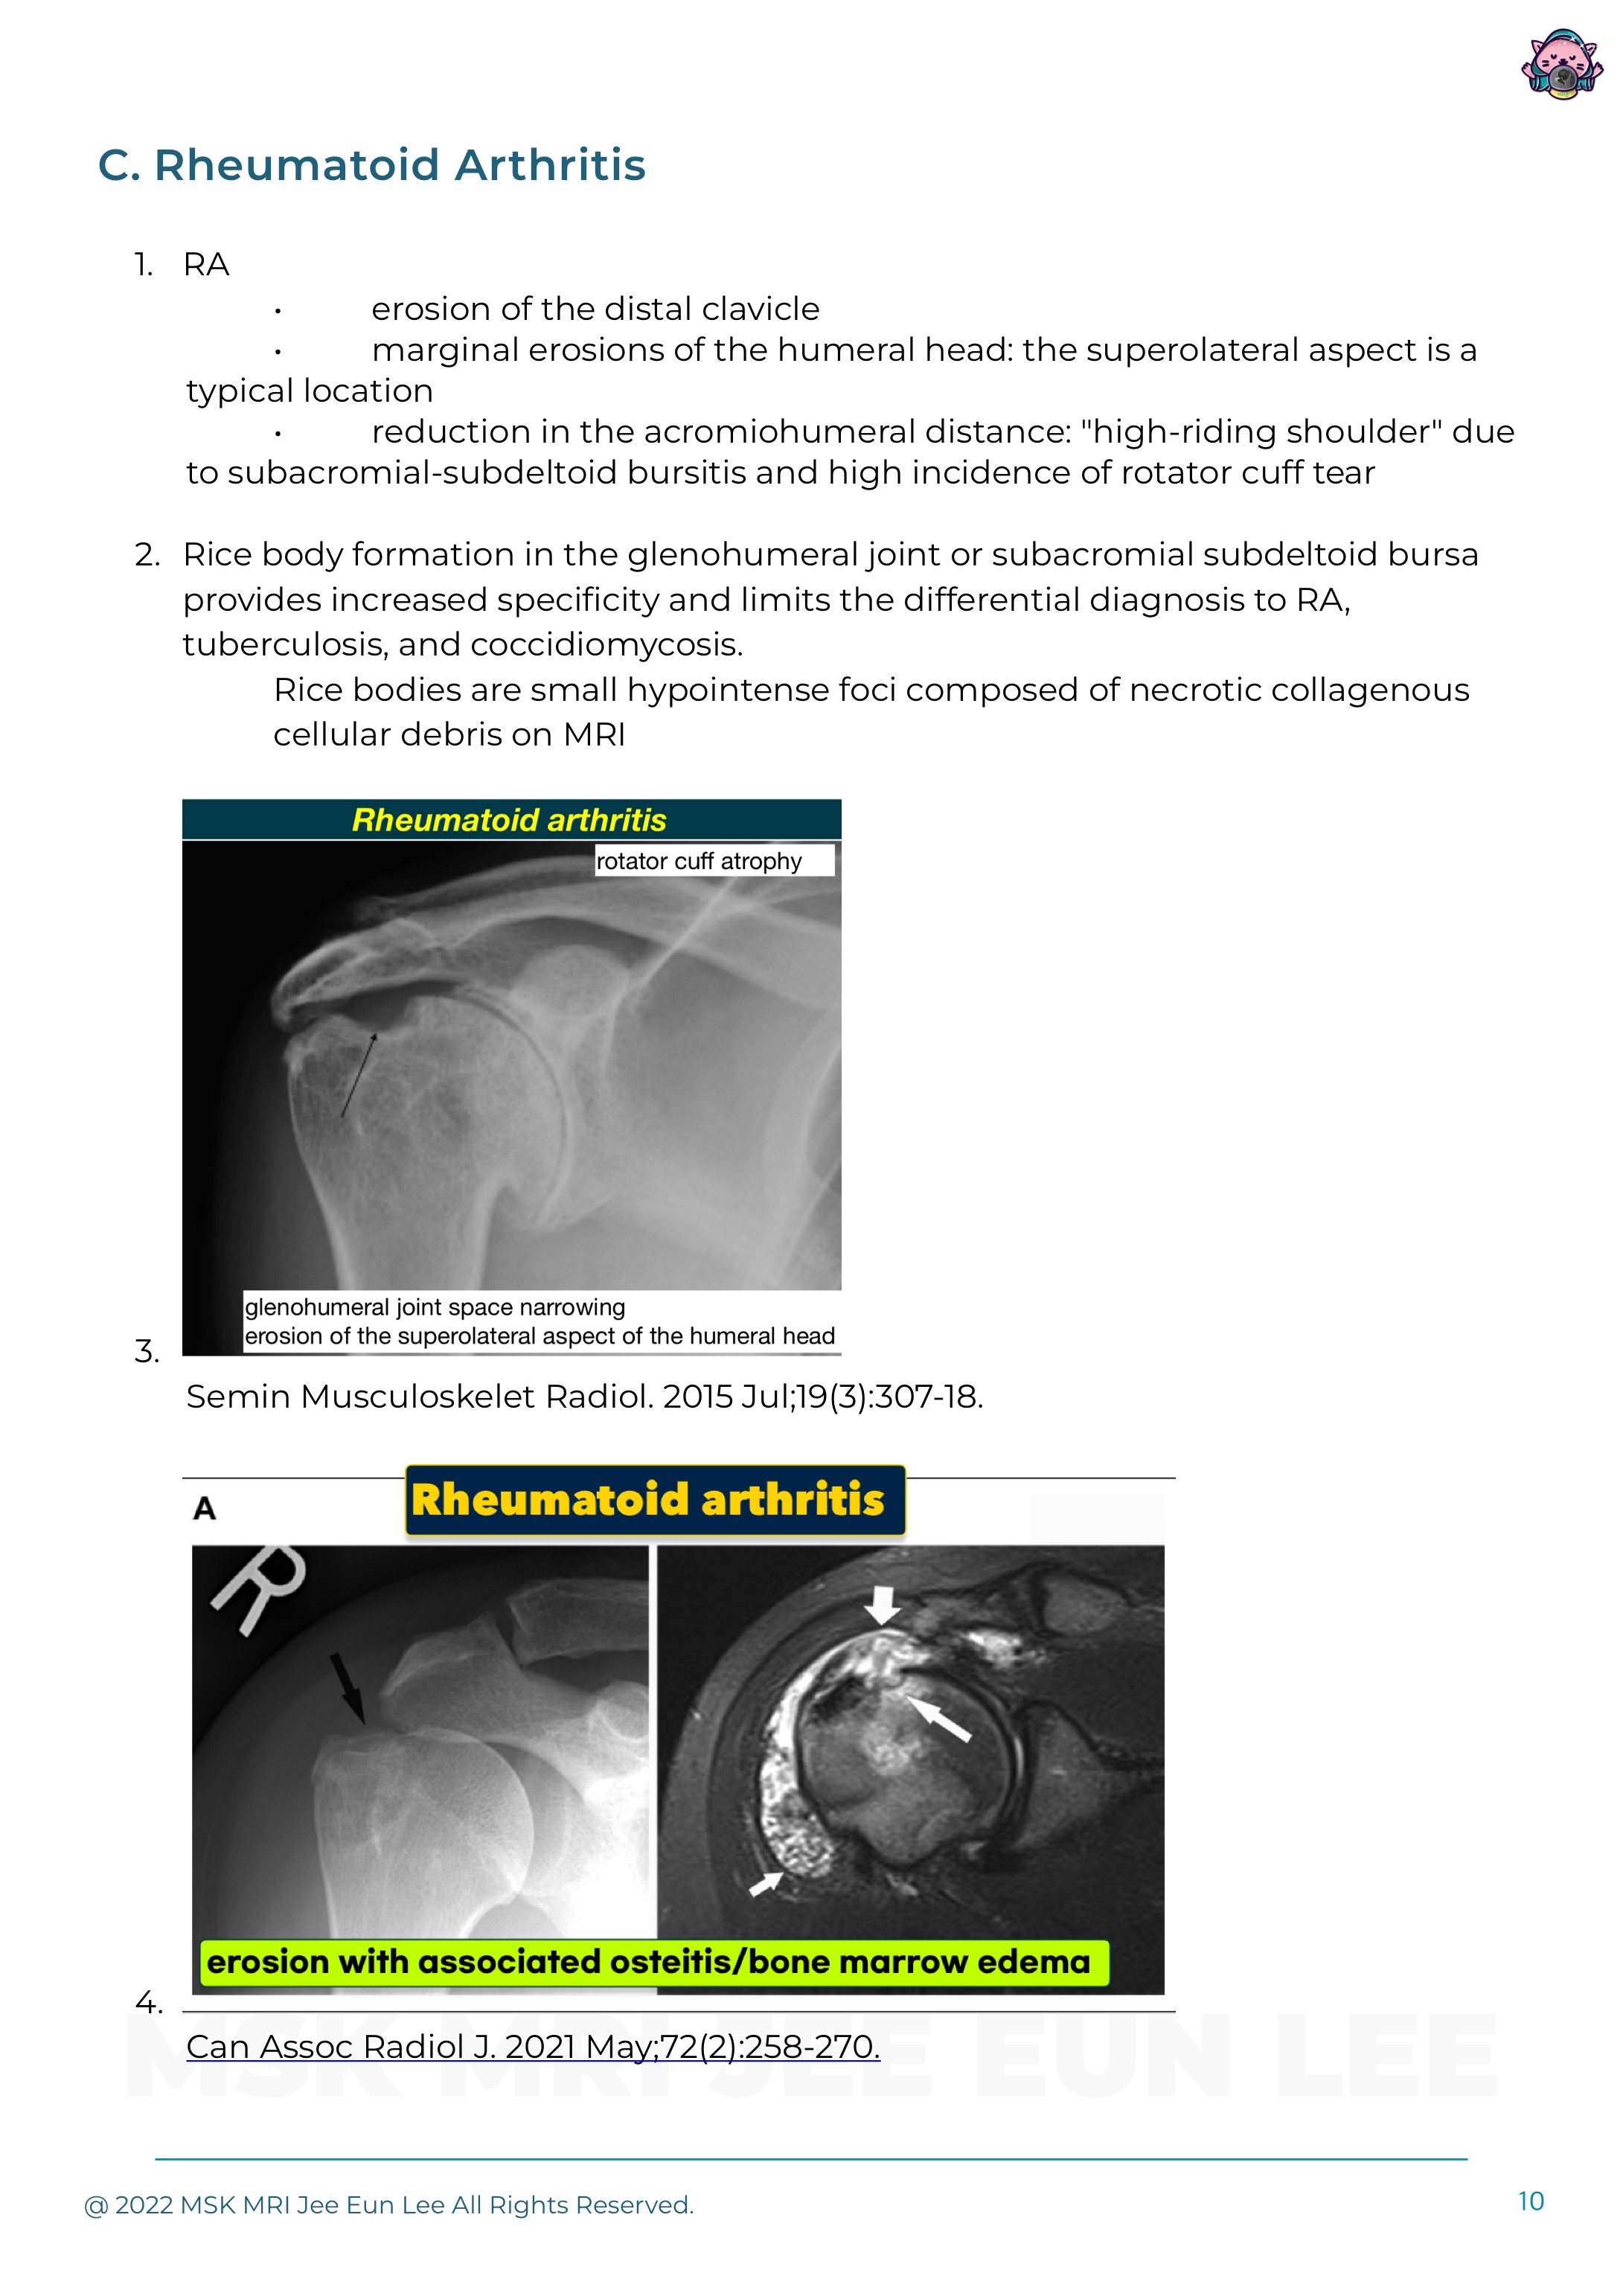

Here is a large superolateral humeral head erosion and synovial thickening and joint effusion. Is this a Hill-Sachs Lesion? Hill-Sachs lesions are strongly associated with anteroinferior glenoid fracture, anteroinferior glenoid labrum tear (Bankart lesion), and joint capsular injury. However, there are several common non-traumatic bones and joint diseases that rarely mimic Hill-Sachs lesions. An..

References Herring A, Davis DL. Mimickers of Hill-Sachs Lesions [Formula: see text]. Can Assoc Radiol J. 2021 May;72(2):258-270. doi: 10.1177/0846537119895751. Epub 2020 Feb 6. PMID: 32063021; PMCID: PMC7415664. โ€‹ Sankaye P, Ostlere S. Arthritis at the shoulder joint. Semin Musculoskelet Radiol. 2015 Jul;19(3):307-18. doi: 10.1055/ s-0035-1549324. Epub 2015 May 28. PMID: 26021591. โ€‹ Fritz LB, Ou..

References Herring A, Davis DL. Mimickers of Hill-Sachs Lesions [Formula: see text]. Can Assoc Radiol J. 2021 May;72(2):258-270. doi: 10.1177/0846537119895751. Epub 2020 Feb 6. PMID: 32063021; PMCID: PMC7415664. Sankaye P, Ostlere S. Arthritis at the shoulder joint. Semin Musculoskelet Radiol. 2015 Jul;19(3):307-18. doi: 10.1055/ s-0035-1549324. Epub 2015 May 28. PMID: 26021591. Fritz LB, Ouelle..